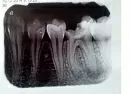

У меня обнаружили 2 кисты на 36. На одном корне киста маленькая, на втором - большая. Снимок прилагается.